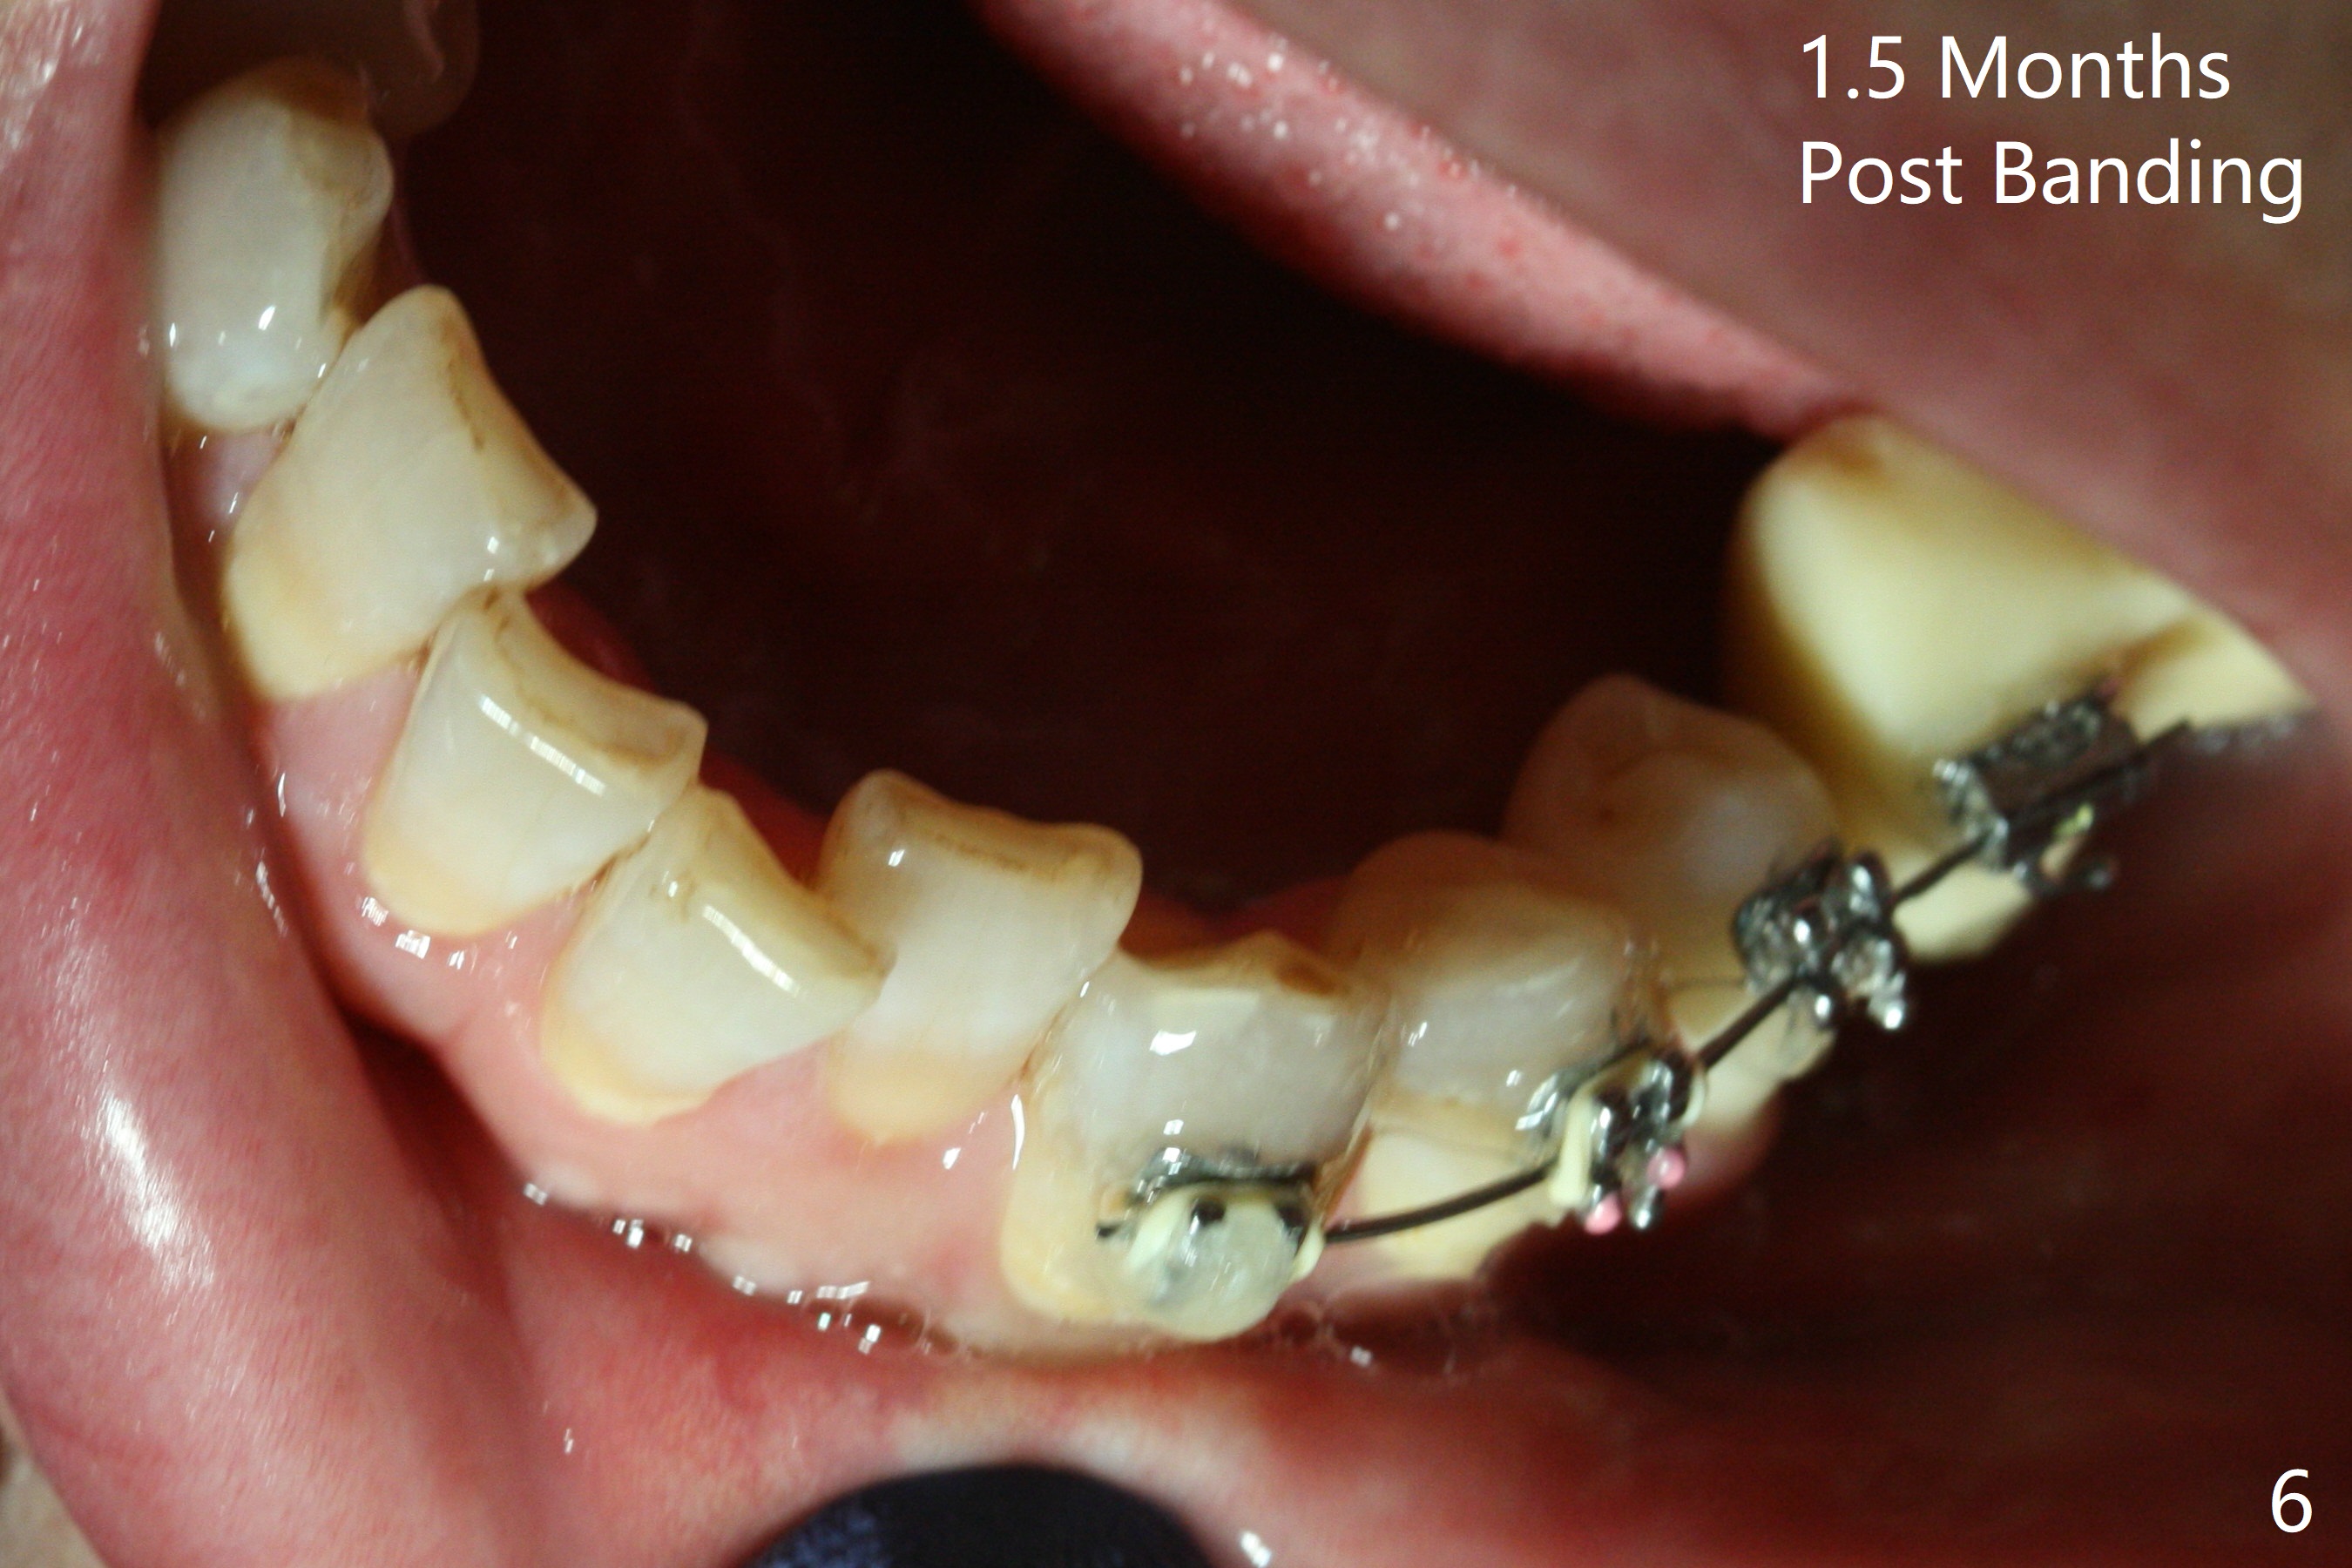

Two weeks post provisionalization over implants at #18 and 19 (4.5 months postop), acrylic is added to the provisional (Fig.1 *) and composite is placed on the other side (Fig.2 *) for clearance (Fig.3). Six days post bracketing, the diastema between LL5 and 6 decreases (Fig.4 between arrows, as compared to Fig.3), suggesting uprighting and distalization of the affected tooth. The diastema increases by trimming the mesial surface of LL6 provisional (Fig.5 *) prior to power chain placement. More acrylic is added to the occlusal surface of LL 6 and 7; more composite to that of UR3 (as compared to Fig.2) for clearance. Power chains change every week. LL5 is uprighted and distalized 1.5 months post banding (Fig.6,7 (14 niti)). Anterior brackets will be placed to correct LL2 cross bite next visit. Three weeks post open coil spring (5 months post initial banding), there is a space between LL2 and 3 (Fig.8) and between LL3/4 (Fig.9). The latter reduces instantly post power chain between LL3 and 6 (Fig.10). There is enough space for LL2 and sling shot is used to correct the cross bite 6.5 months post initial banding (Fig.11). The cross bite is corrected in 1.5 months after occlusal clearance is established (Fig.12). The lower left alignment is within normal limit, although in cross bite with the opposing dentition, immediate post molar crown cementation (Fig.13).